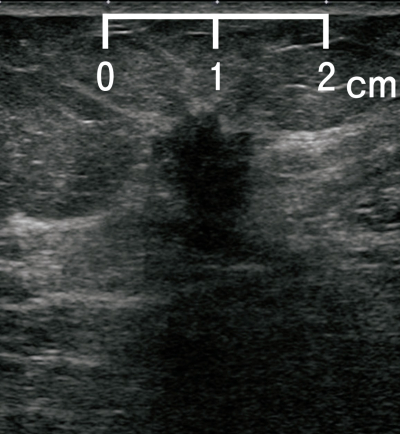

77歳の女性。肺がん検診の低線量CTで左乳房腫瘤を指摘されたため受診した。マンモグラム及び乳房超音波像を別に示す。

次に行うのはどれか。

c. 経皮的針生検